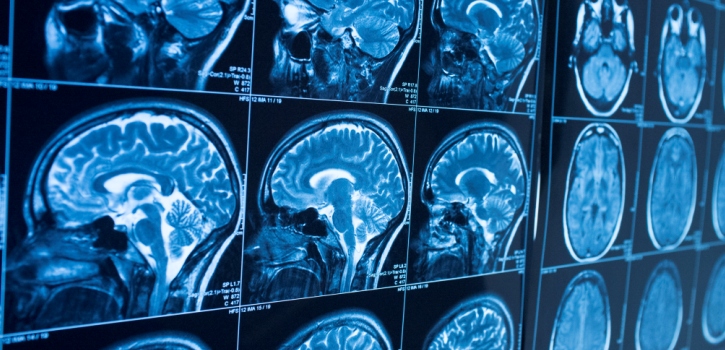

L’ictus è la seconda causa di morte a livello mondiale, con un’incidenza di 6,2 milioni di casi.

Quali fattori incidono sullo sviluppo di un ictus?

Uno dei motivi principali per cui la fibrillazione arteriale incide notevolmente sullo sviluppo di un ictus è la sua diagnosi tardiva, resa difficile dall’assenza di sintomi, ma aggravata anche da una scarsa consapevolezza dei medici generali e dell’opinione pubblica.

Come prevenire la formazione di un ictus?

L’utilizzo di farmaci anticoagulanti potrebbe sicuramente aiutare nella gestione della malattia, ma le controindicazioni, il rischio di sanguinamento e il rifiuto dei pazienti di assumere i farmaci (motivo dominante per cui non vengono impiegati nella prevenzione contro l’ictus) frenano le possibilità di imporre una svolta nel trattamento delle complicazioni.

È dunque importante informarsi e conoscere quali sono le cause che possono far sviluppare un ictus, ma soprattutto è necessario personalizzare le cure e le attenzioni per i pazienti che possono presentare, a causa dell’anamnesi o per semplice incidenza di fattori, una predisposizione alla patologia.